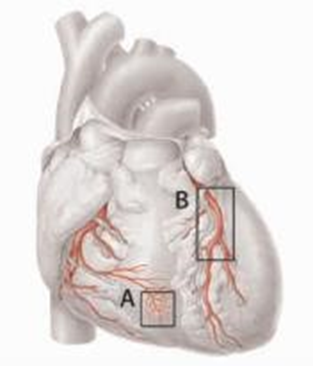

Veranderingen in de vaatwand kunnen ervoor zorgen dat de kleine bloedvaatjes niet goed verwijden (figuur 1). Het gevolg is dat de hartspier bij inspanning te weinig bloed en dus zuurstof krijgt. Hierdoor kun je dezelfde pijn op de borst ervaren als bij ernstige vernauwingen in de kransslagaders. Echter, treden de klachten bij de kleinere vaatjes eerder op bij normale dagelijkse activiteiten of bij stress. De klachten duren meestal langer dan 10 minuten, en kunnen ook aanhouden na het stoppen van de activiteiten. Soms duren ze zelfs langer dan 30 minuten. Het niet goed werken van de allerkleinste vertakkingen van de kransslagaders noemt men ook wel CMD. Dat staat voor coronaire microvasculaire dysfunctie.

Figuur 1 A: kleine bloedvaatjes van het hart. B: kransslagaders